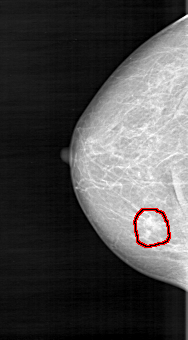

D_4103_1.RIGHT_CC

FILE: D_4103_1.RIGHT_CC.OVERLAY

TOTAL_ABNORMALITIES 1

ABNORMALITY 1

LESION_TYPE CALCIFICATION TYPE PUNCTATE DISTRIBUTION CLUSTERED

LESION_TYPE MASS SHAPE IRREGULAR MARGINS ILL_DEFINED

ASSESSMENT 3

SUBTLETY 3

PATHOLOGY MALIGNANT

TOTAL_OUTLINES 1

BOUNDARY